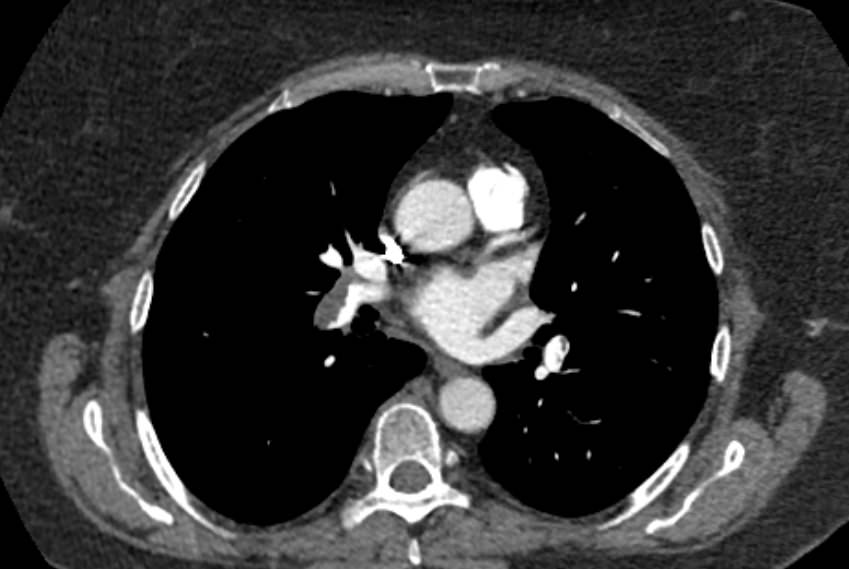

Легочный ствол отходит от правого желудочка сердца, затем разветвляется на правую и левую легочные артерии, которые несут венозную кровь от всего тела к легким для насыщения ее кислородом. Легочные артерии разветвляются на сосуды меньшего калибра, самые мелкие из которых – легочные капилляры – образуют густую сосудистую сеть, где непосредственно происходит обогащение крови кислородом.

Патология легочной артерии может проявляться повышением давления внутри просвета сосудов. Это состояние называется легочной гипертензией и развивается на фоне заболеваний сердечно-сосудистой системы, обструктивных заболеваний легких. Кроме того, легочная гипертензия сопутствует порокам развития дыхательной системы, клапанов сердца, а также может быть следствием многих других болезней, например, гемолитической анемии и системных заболеваний соединительной ткани.

Еще к частым патологиям легочной артерии относится стеноз (сужение просвета) легочной артерии, который может быть врожденным и приобретенным, и тромбоэмболия легочной артерии (ТЭЛА).

Наиболее информативным, при этом быстрым и неинвазивным (то есть без вмешательства в организм пациента), методом диагностики патологии легочной артерии является мультиспиральная компьютерная томография (КТ-ангиография). Методика основана на использовании рентгеновского излучения в сочетании с цифровой обработкой данных для получения трехмерных изображений сосудистой системы.

Для визуализации кровеносных сосудов в обязательном порядке применяется контрастное усиление. Для этого в вену пациента вводится йодсодержащий контрастный препарат, который попадая в кровоток активно поглощает рентгеновские лучи и ярко контрастирует сосудистую систему, в том числе легочной артерии, на фоне окружающих тканей. Использование контраста дает возможность визуализировать даже мелкие артерии и выявить патологию.

В наших диагностических центрах КТ-ангиография легочной артерии проводится на современных мультиспиральных компьютерных томографах экспертного уровня TOSHIBA AQUILION. Оснащение аппаратов позволяет получать детальные снимки и трехмерные изображения сосудистой системы легочной артерии, при этом применение скоростной мультисрезовой методики сканирования значительно снижает уровень лучевой нагрузки на пациента.